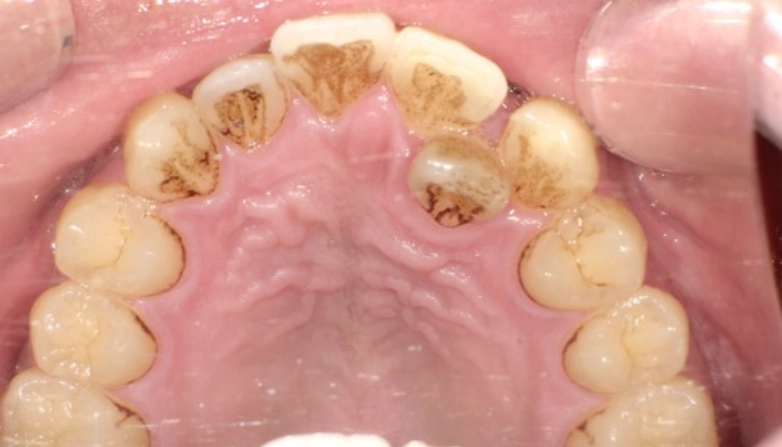

症例4

before

after

| 主 訴 | 着色を落としたい |

| 治療期間 | 通院 1回 |

| 治 療 費 | 1回 11,000円(税込) |

| 治療内容 | PMTC+エアフロー |

| 治療のリスク | 歯自体の色を白くすることはできない。 生活習慣によってはしばらくすると再び着色することがある。 術後、しみることが稀にある。 |